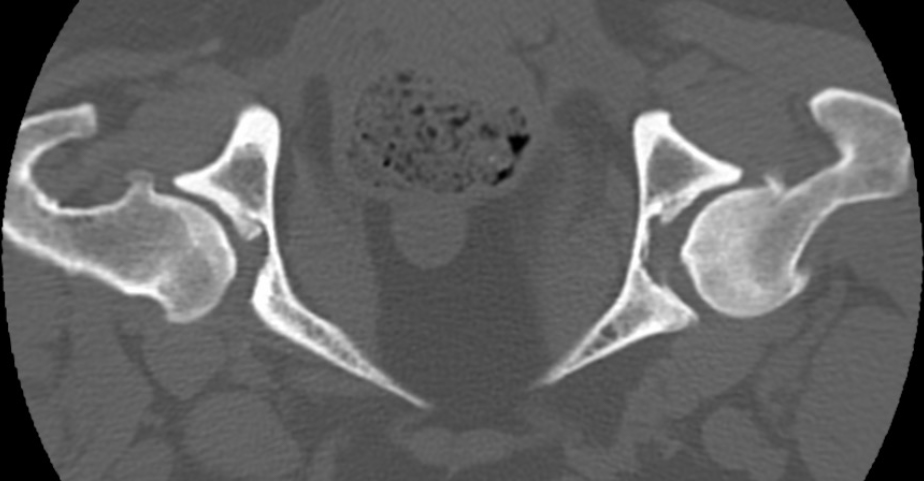

There is bilateral mild periarticular new bone formation at the femoral heads and necks and cranial and caudal acetabular margins (see image below). There are mineral attenuating foci noted at the level of the right lesser trochanter.

- Bilateral osteoarthrosis of the coxofemoral joints.